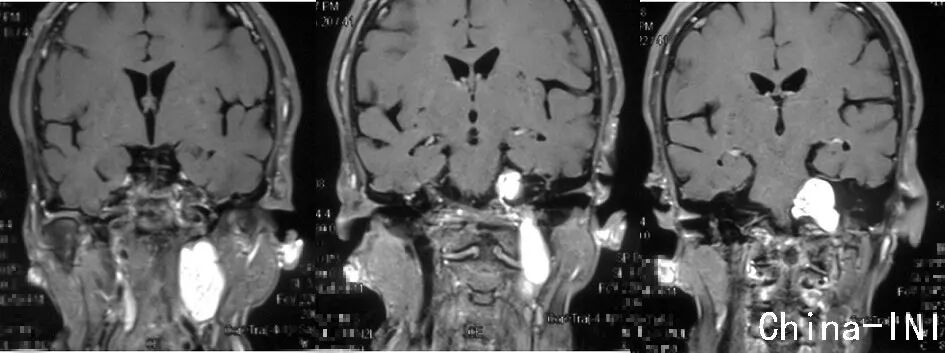

MRI轴位增强像示左侧颈静脉孔区神经鞘瘤,肿瘤呈哑铃型,同时侵及颅内、颈静脉孔及颈部,属于Samii颈静脉孔神经鞘瘤分型之D型,Fukushima分型之C型。

MRI冠状位增强像示肿瘤同时波及颅内、颈静脉孔及颈部,上端接近小脑幕水平,下端达第三颈椎水平。

术后MRI复查,显示肿瘤切除彻底;